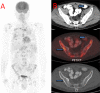

Case presentation: A 62-year-old patient previously diagnosed and treated due to pulmonary sarcoidosis has developed an omental metastatic lesion 13 years after having undergone open extraperitoneal partial nephrectomy for T1 clear-cell RCC. Constitutional symptoms and imaging findings that were attributed to the presence of a sarcomatoid paraneoplastic syndrome triggered by the development this metastatic focus complicated the diagnostic work-up. Biopsy of the [18F]-fluorodeoxyglucose (+) lesions confirmed the diagnosis of metastatic RCC and the patient was managed by the resection of the omental mass via near-total omentectomy followed by targeted therapy with a tyrosine kinase inhibitor.

Conclusion: To our knowledge, this is the first reported case of metachronously developed, isolated omental metastasis of an initially T1 clear-cell RCC. Constitutional symptoms, despite a long interval since nephrectomy, should raise the possibility of a paraneoplastic syndrome being associated with metastatic RCC. Morphological and molecular imaging studies together with histopathological documentation will be diagnostic.